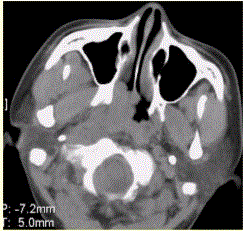

问题 患者男,45岁,鼻塞、涕中带血2周。查体颈部淋巴结增大。专科检查发现,鼻咽腔黏膜肿胀,左侧咽隐窝消失。CT表现如下图。 临床拟诊为

选项 A.鼻窦炎 B.内翻性乳头状瘤 C.纤维血管瘤 D.鼻咽癌 E.淋巴瘤 F.鼻息肉

答案 D